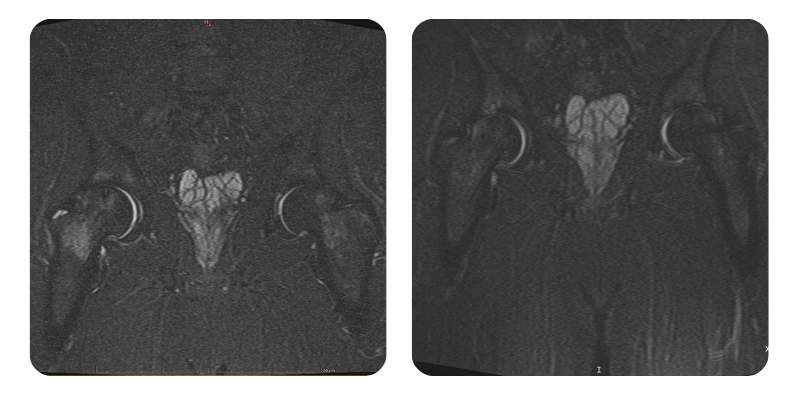

Prima

Dopo

H.V., 46 anni - Necrosi asettica della testa del femore, stadio III destro.

Risultato: Al controllo si osserva riduzione dell'edema del 50%, con corrispondente riduzione clinica del dolore da 9/10 iniziale a 6-7/10 post-trattamento. Si evidenzia inoltre miglioramento della mobilità di circa il 40%; si raccomanda prosecuzione della terapia iperbarica.

Dopo il secondo ciclo, il paziente riferisce riduzione del dolore da 8-9/10 a 2-3/10, presente solo in caso di sforzo intenso; a riposo e con sforzo moderato il dolore è assente. Il sonno è diventato regolare, potendo dormire sul fianco senza disagio.

Si osserva, sia clinicamente sia all'imaging, un recupero del 90% con remissione dell'edema e persistenza delle geodi. Si raccomanda RMN di controllo a 1 anno, controlli al bisogno e riduzione del peso corporeo per mantenere uno stile di vita sano ed equilibrato.